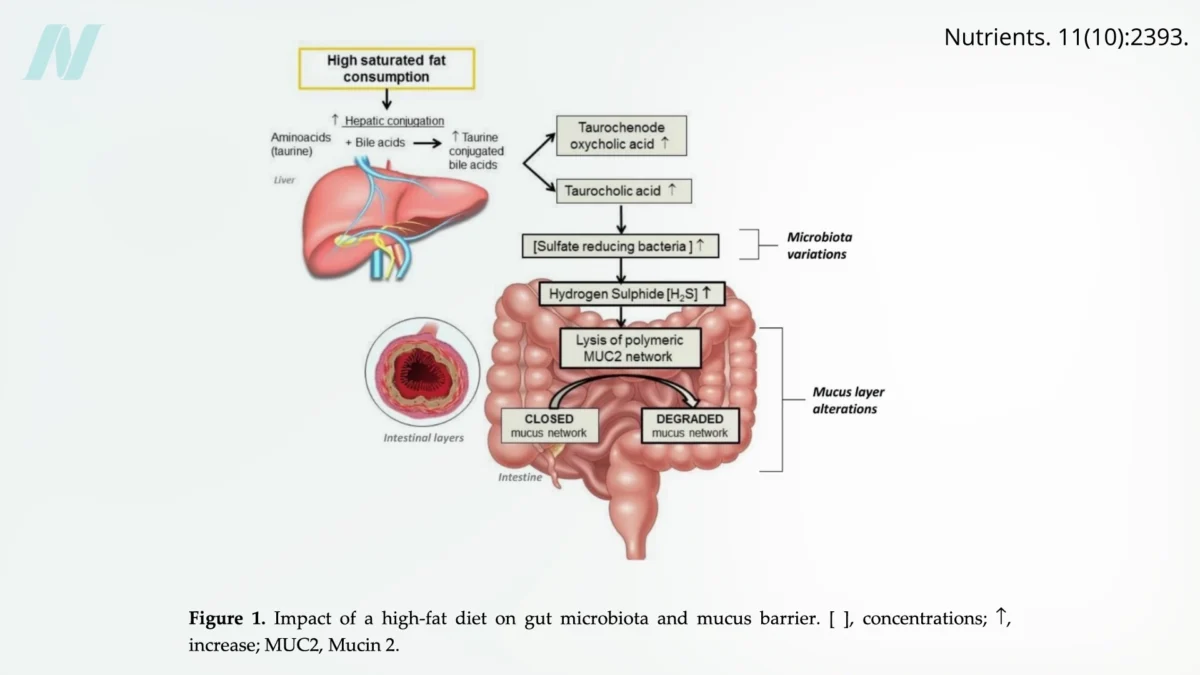

Onions: Unpacking the Evidence from Randomized Human Trials for Health Benefits

Onions, a staple in kitchens worldwide and a cornerstone of countless culinary traditions, have long been lauded for their potential health-promoting properties. While anecdotal evidence and traditional medicine have often…